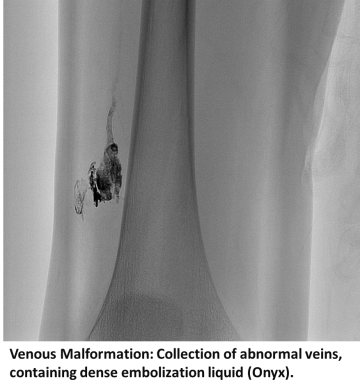

Venous malformations are abnormally enlarged veins present at birth. Blood flows through venous malformations relatively slowly and they are typically asymptomatic. If present superficially, venous malformations can manifest as soft blue patches or masses that can occur anywhere in the body. Lumps on the face, limbs, or trunk are common locations where venous malformations occur.

- Venous and lymphatic malformation embolization